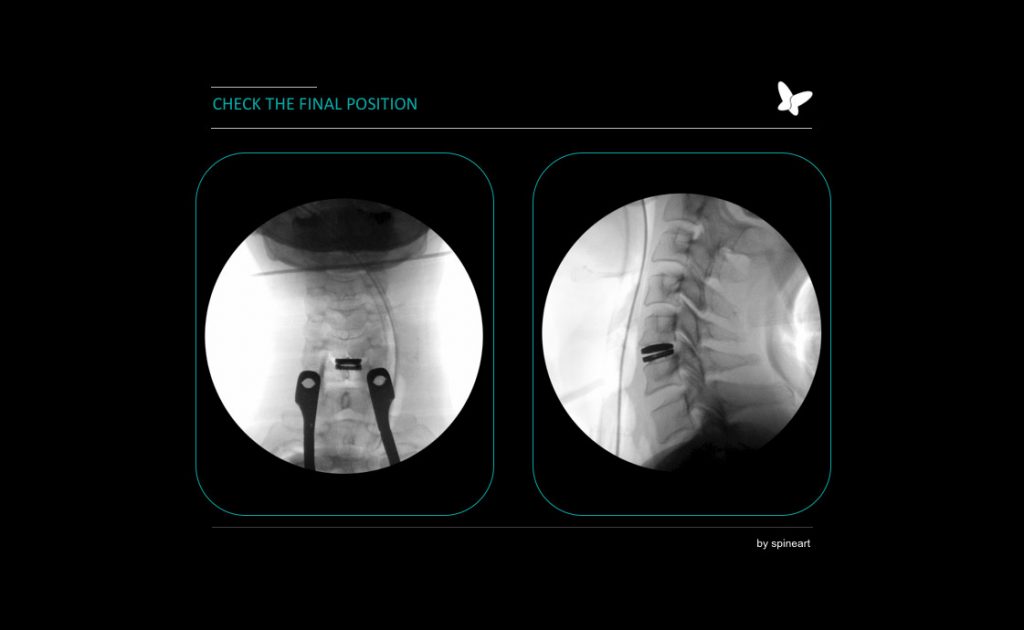

Cervical Disc Replacement Surgery

Cervical disc replacement surgery involves removing a diseased cervical disc and replacing it with an artificial disc…